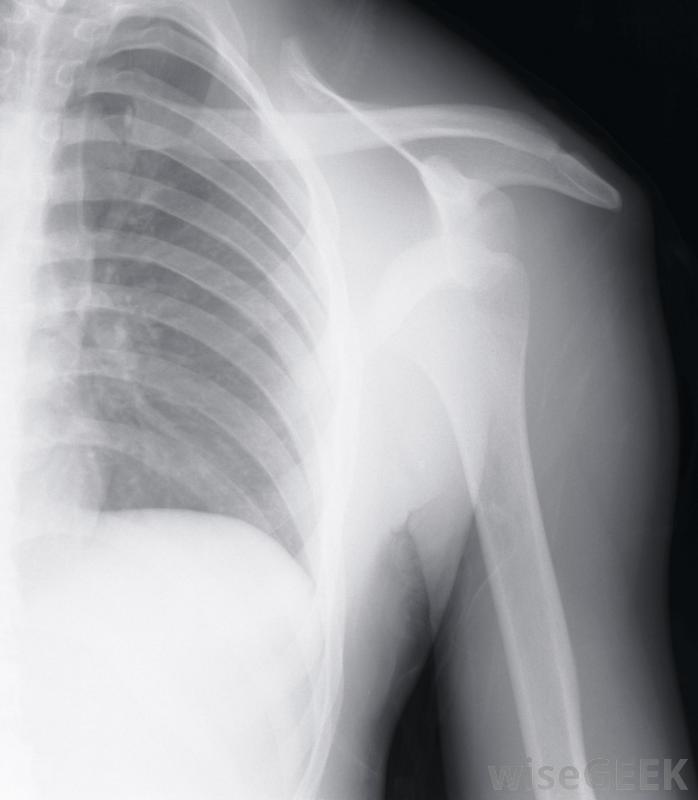

对于侧睡的人来说,睡在受影响的肩膀上会加重滑囊炎,因此理想情况下应避免使用。如果休息和结冰不能帮助治愈滑囊炎的疼痛,应寻求医疗帮助。如果肩关节红肿,应立即寻求专业医护人员;这通常表明感染。医生会为感染性肩滑囊炎开抗生素治疗医生也可以进行一些诊断测试,包括血液测试、超声波扫描或x光检查。

肩关节x光检查可帮助指示肩关节滑囊炎的严重程度和正确的治疗。